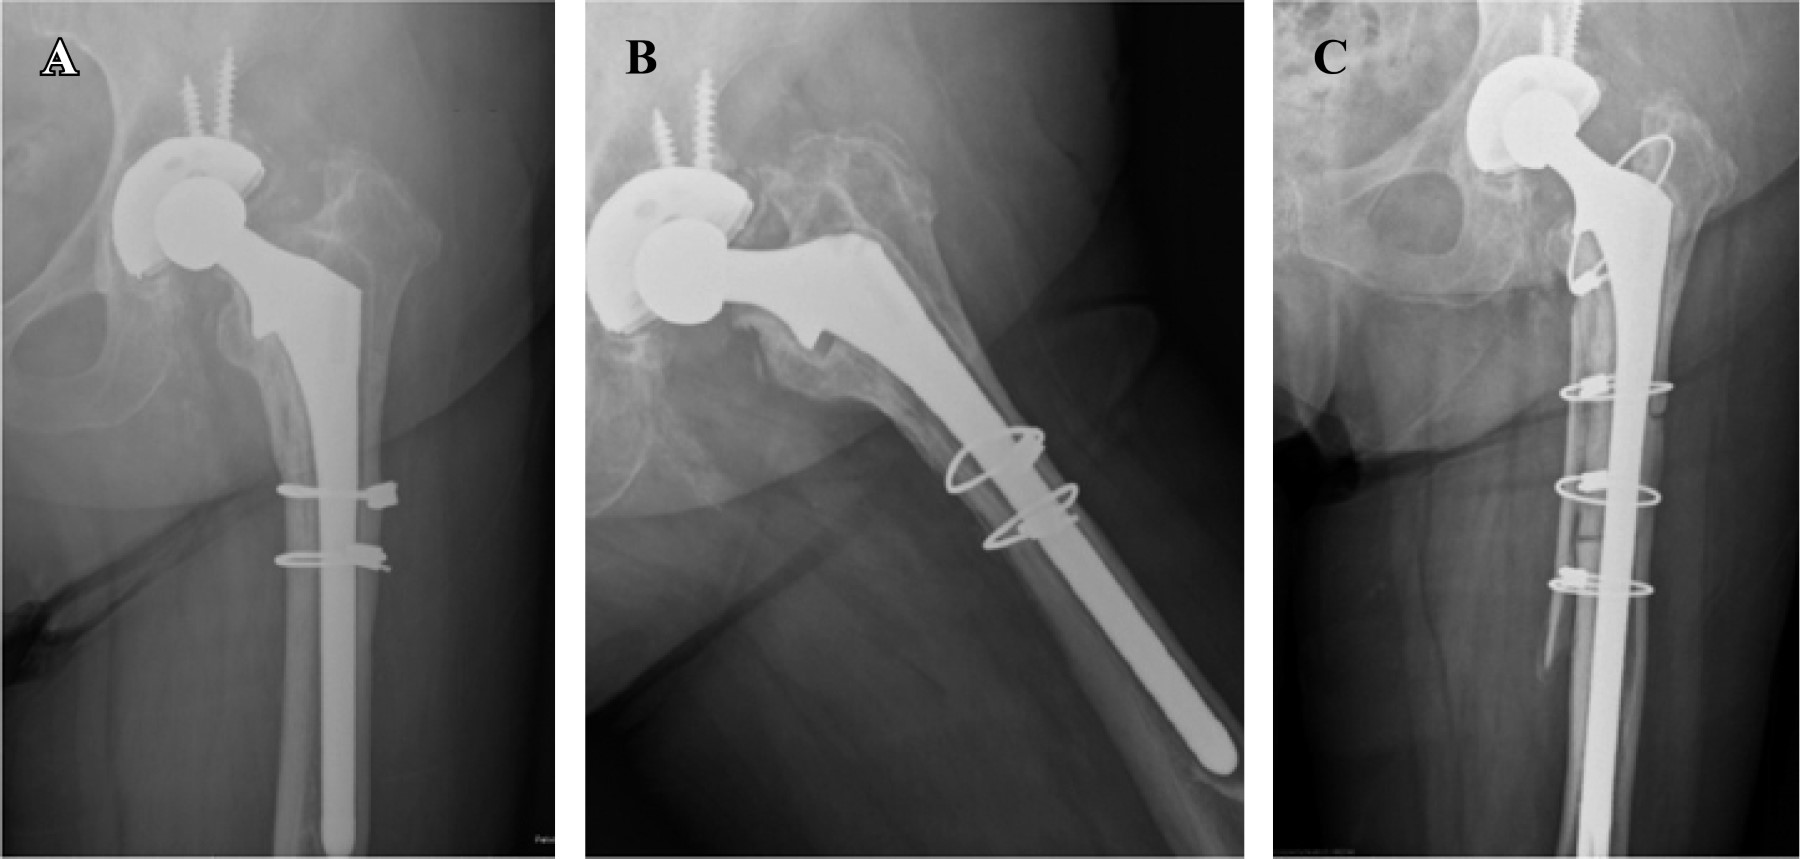

En todas se usó el abordaje posterolateral a la cadera. Realizamos una osteotomía trocantérica ampliada (OTA) en 19 casos (24.4%). La fijación de la osteotomía se realizó en todos los casos mediante cerclajes asociando en tres pacientes osteosíntesis con placa trocantérica y en 11 casos aloinjerto estructural criopreservado (Figura 1). En 42 casos se llevó a cabo de forma concomitante una revisión del componente acetabular, implantándose en 17 casos cotilos de doble movilidad, en 24 cotilos hemiesféricos monopolares y en un caso un cotilo retentivo.

Aunque se han reportado casos con rotura del vástago en pacientes con defectos óseos severos, no encontramos esta complicación en nuestra serie. Busch,32 en su serie de 219 revisiones con vástagos cilíndricos de recubrimiento completo, identifica cinco roturas de vástagos (2.3%), las asocia a un defecto de soporte óseo proximal a un IMC > 30 y al uso de una OTA. Las tensiones más altas dadas en el vástago son a nivel del sitio de la osteotomía, por lo que el uso de aloinjerto estructural reducirá la tensión en el vástago 48%, recomendando esta técnica en pacientes con un defecto óseo severo asociado a una OTA. En nuestra serie realizamos 19 OTAs, siendo reparadas en todos los casos mediante cerclajes asociados en tres ocasiones a placa de grandes fragmentos y en 11 a aloinjerto estructural de banco (Figura 1).